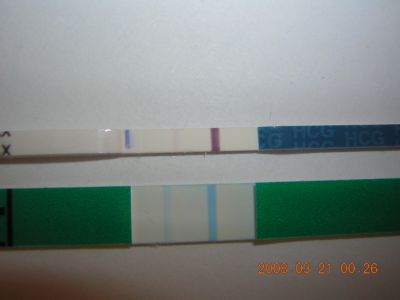

2008.03.21 08:41

2008.03.21 10:50

2008.03.21 14:30

2008.03.21 20:52

2008.03.21 23:37